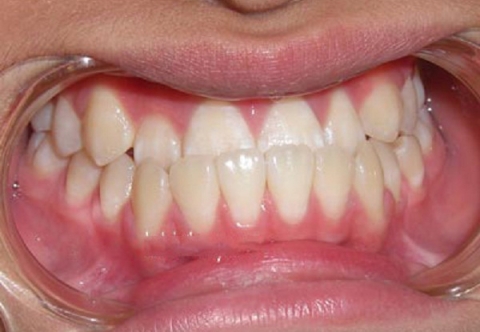

Ngoài việc thắc mắc chụp răng thép cho bé giá bao nhiêu thì các phụ huynh còn lo lắng chụp thép răng sữa có ảnh hưởng gì đến hàm răng của con không. Việc chụp thép sẽ không ảnh hưởng gì đến quá trình thay răng, răng thép sẽ thay cùng răng sữa trong quá trình mọc răng vĩnh viễn.

Với các lợi ích như: bảo vệ và nâng đỡ mô răng, độ thẩm mỹ cao, chống oxy hóa trong miệng, thích hợp cho răng sâu kẽ còn tủy. Chụp răng sữa cho bé được kiểm chứng và chứng nhận không gây kích ứng cho răng và an toàn trong khoang miệng hoàn toàn không ảnh hưởng gì đến con nên bố mẹ có thể yên tâm.